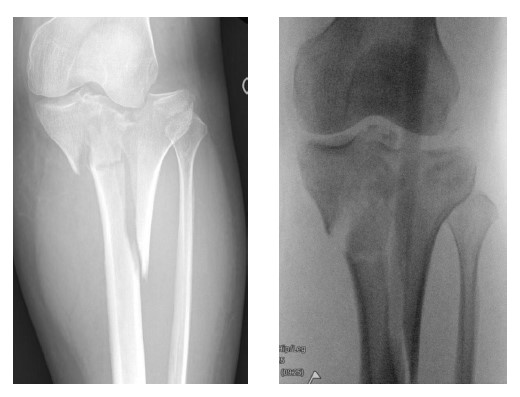

• A 40-year-old female sustained a displaced tibial plateau fracture (fig.1) with marked soft-tissue swelling, conferring ~50% ACS risk.